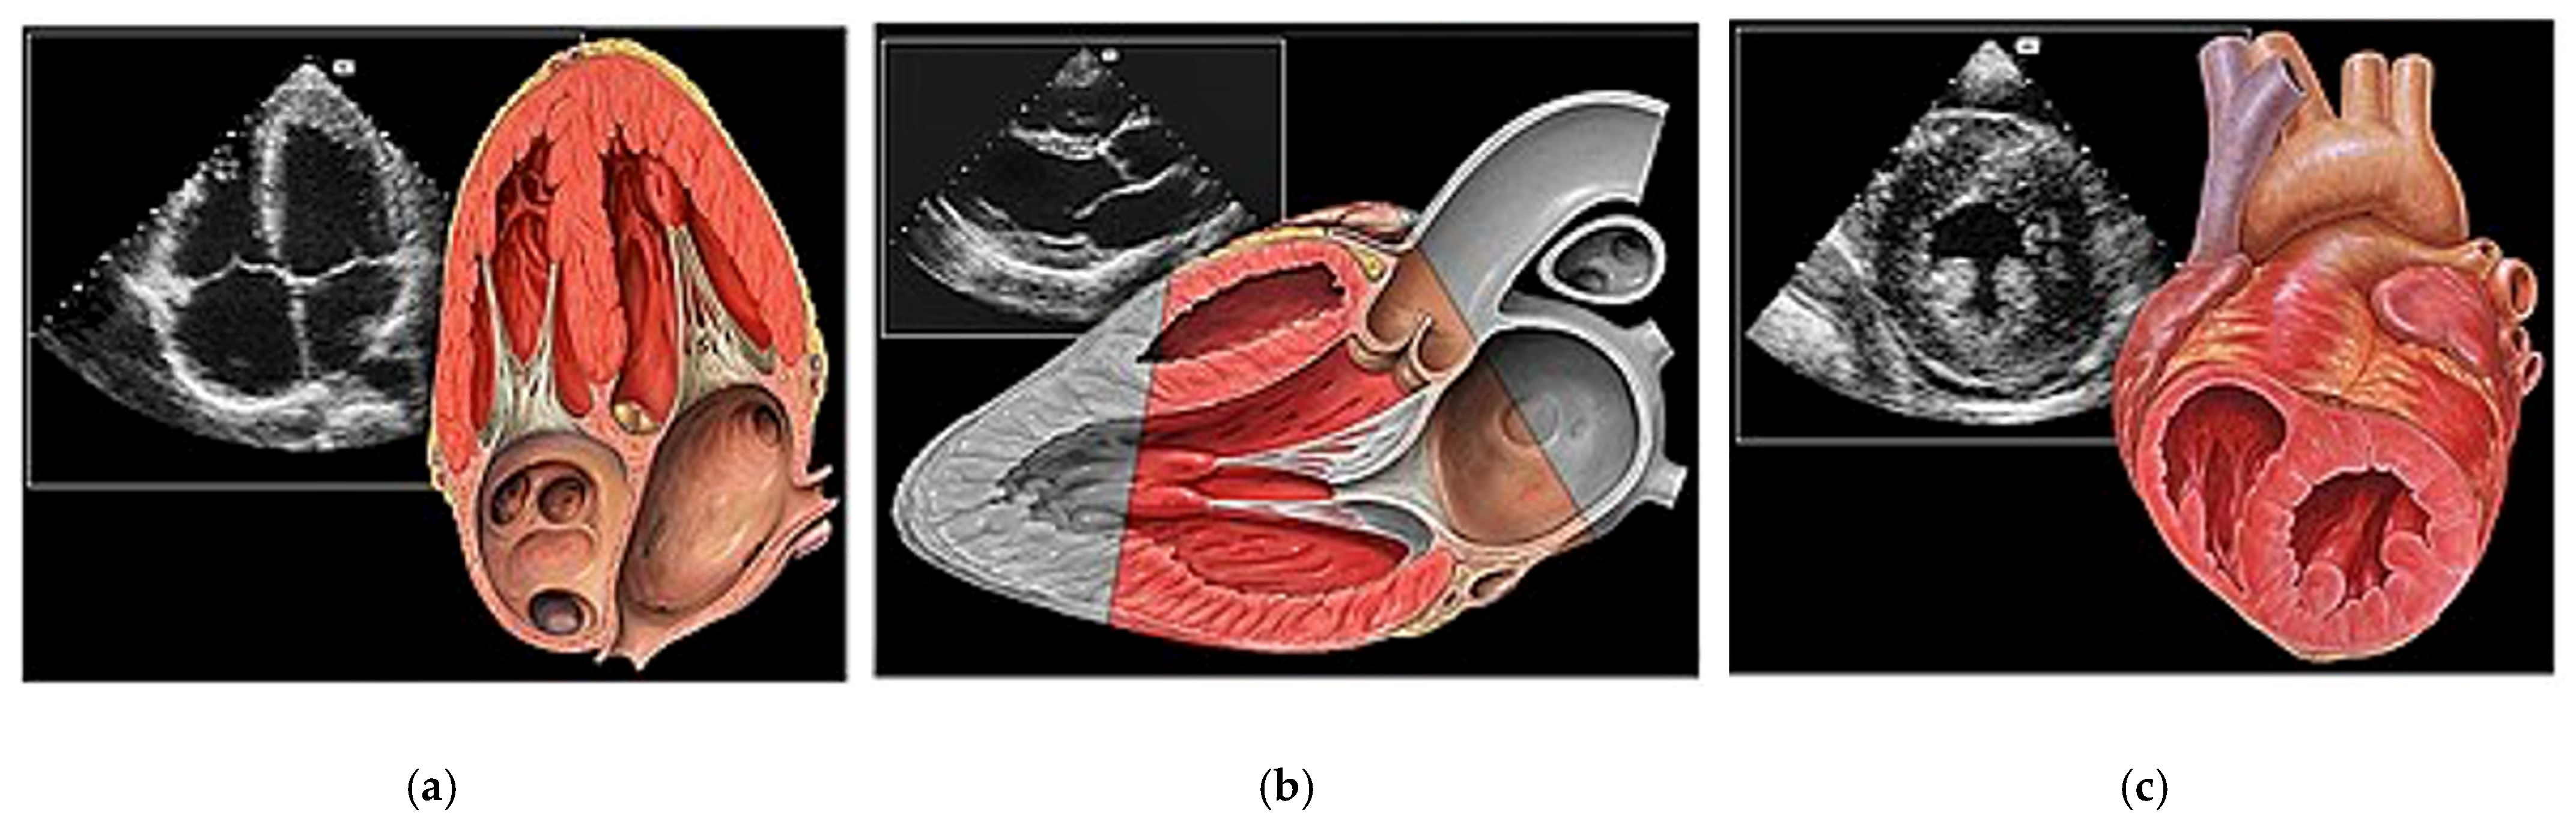

- Basic Cardiac Views (Figure 3)The standard echocardiographic views required to assess cardiac valvular structure and function include the parasternal long-axis (PLAX), parasternal short-axis (PSAX), apical four-chamber (A4C) and subcostal (SC) views. These views facilitate the visualisation of the aortic, mitral, tricuspid, and pulmonic valves, thus enabling the identification of valvular abnormalities [38].